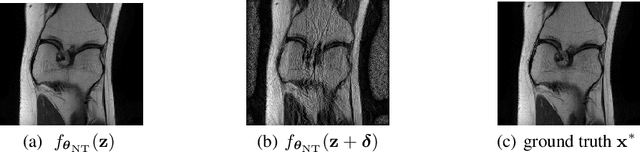

Although deep learning (DL) has received much attention in accelerated magnetic resonance imaging (MRI), recent studies show that tiny input perturbations may lead to instabilities of DL-based MRI reconstruction models. However, the approaches of robustifying these models are underdeveloped. Compared to image classification, it could be much more challenging to achieve a robust MRI image reconstruction network considering its regression-based learning objective, limited amount of training data, and lack of efficient robustness metrics. To circumvent the above limitations, our work revisits the problem of DL-based image reconstruction through the lens of robust machine learning. We find a new instability source of MRI image reconstruction, i.e., the lack of reconstruction robustness against spatial transformations of an input, e.g., rotation and cutout. Inspired by this new robustness metric, we develop a robustness-aware image reconstruction method that can defend against both pixel-wise adversarial perturbations as well as spatial transformations. Extensive experiments are also conducted to demonstrate the effectiveness of our proposed approaches.